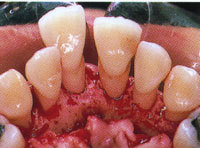

▼STEP4 歯周外科中

歯周外科のステップ

1.SRP後のプロービング診査で出血が認められます。

2.根面を直視するため肉牙組織の除去を行ないます。

3.歯槽骨を被覆するように縫合します。

4.術後の診査では炎症がなくなり、プロービング時に出血を認めません。